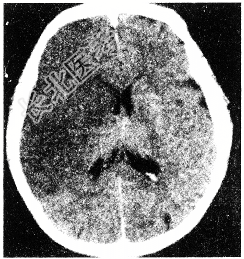

- [材料题] 男性患者,56岁。半月前无明确诱因出现头晕症状,伴左下肢无力,左上肢发胀,双手麻木,症状呈进行性加重。查体:除左下肢肌力Ⅳ级外无其他阳性体征。

- 单项选择题1.行头颅CT检查提示可能诊断为

A、颅内肿瘤

B、高血压脑出血

C、脑囊肿

D、脑脓肿

E、脑梗死